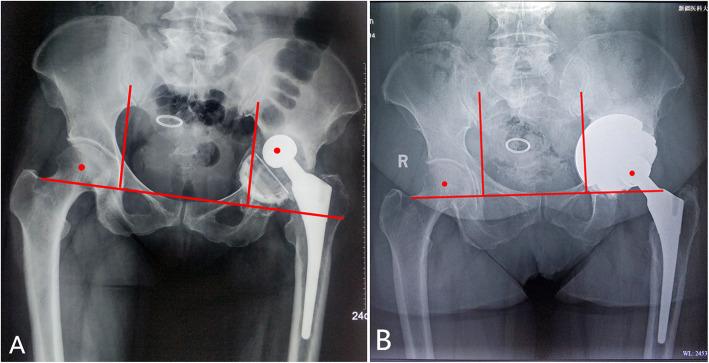

Between January 2015 and December 2018, the multicup reconstruction was performed in 21 patients with severe protrusio acetabular defects. The revision shell, plus two similar porous acetabular components was implanted into the initial shell to create a "multicup" construct. The functional outcomes were evaluated in terms of the Harris Hip Score. Acetabular loosening, restoration of hip center of rotation, and bone ingrowth etc., were radiographically assessed. The survival rate of the implants was also evaluated.

A followup lasting a mean time of 31 months (range, 18-57 months) revealed that the average Harris Hip Score improved from preoperative 37.0 ± 7.1 to postoperative 76.4 ± 9.0. There were no revisions due to acetabular loosening. The horizontal offset increased by an average of 14 mm, and the vertical offset decreased by an average of 18 mm. Eighteen of the 21 patients (86 %) met at least 3 of 5 criteria associated with bone ingrowth. The survivorship free from re-revision for acetabular loosening after 2 years was 100 %.

2015年1月至2018年12月期间,对21例髋臼严重内陷缺损患者进行多杯重建。将翻修髋臼杯与另外两个类似的多孔髋臼部件植入初始髋臼杯中,构建“多杯”结构。根据Harris髋关节评分评估功能结果。通过影像学评估髋臼松动、髋关节旋转中心的恢复以及骨长入等情况。同时评估植入物的生存率。

平均随访31个月(范围18 - 57个月)显示,Harris髋关节评分平均从术前的37.0±7.1提高到术后的76.4±9.0。没有因髋臼松动而进行翻修的病例。水平偏移平均增加14 mm,垂直偏移平均减少18 mm。21例患者中有18例(86%)至少满足与骨长入相关的5项标准中的3项。2年后因髋臼松动无需再次翻修的生存率为100%。